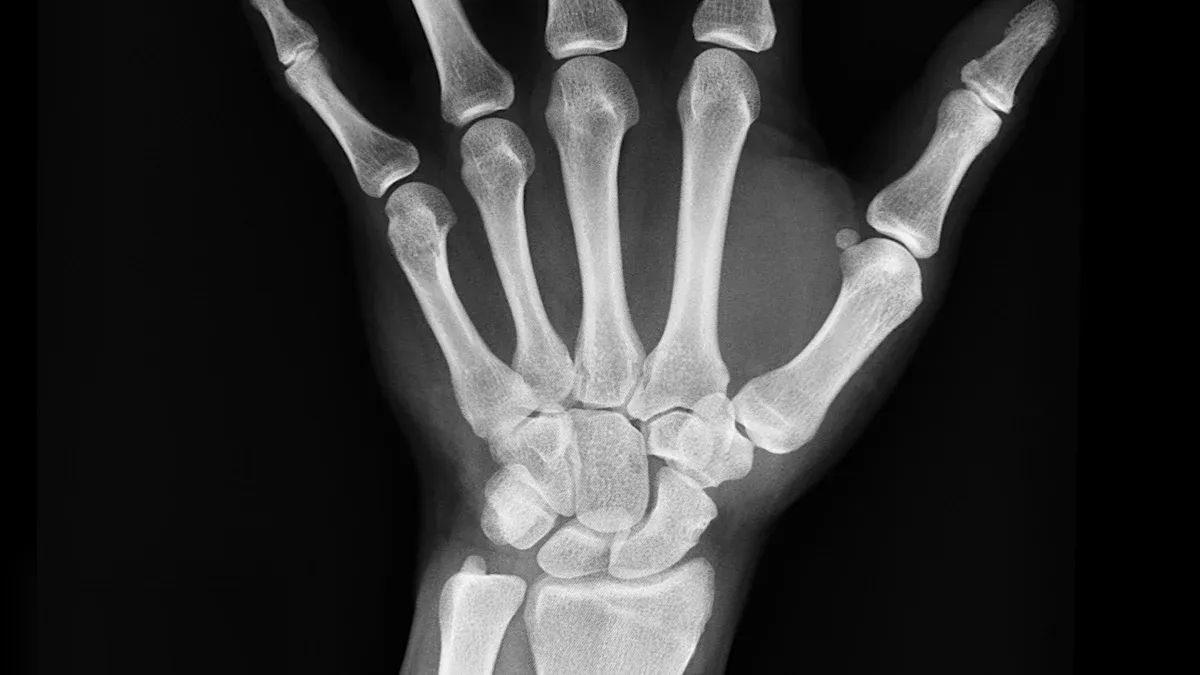

You want strong bones that last a lifetime. Vitamin D3 and K2 work together to help you build healthy bones and keep them strong. When you take vitamin D3, your body absorbs more calcium from food. K2 makes sure that calcium goes into your bones, not your arteries. This teamwork helps you promote bone health and avoid problems later in life.

You want to avoid broken bones as you get older. Vitamin D3 and K2 help lower your risk of fractures by making your bones tougher. D3 helps your body absorb calcium, while K2 activates proteins that move calcium into your bones.

You can see how these vitamins help your bones use calcium the right way. Studies show that people who take vitamin D3 (800-1000 IU/day) have a pooled relative risk of 0.87 for fractures, which means fewer broken bones compared to those who do not supplement.

Regular use of vitamin D3 and K2 may improve early bone fusion rates in people with osteoporosis. Scientists still study the long-term effects, but you can feel confident that these vitamins support your bone health.